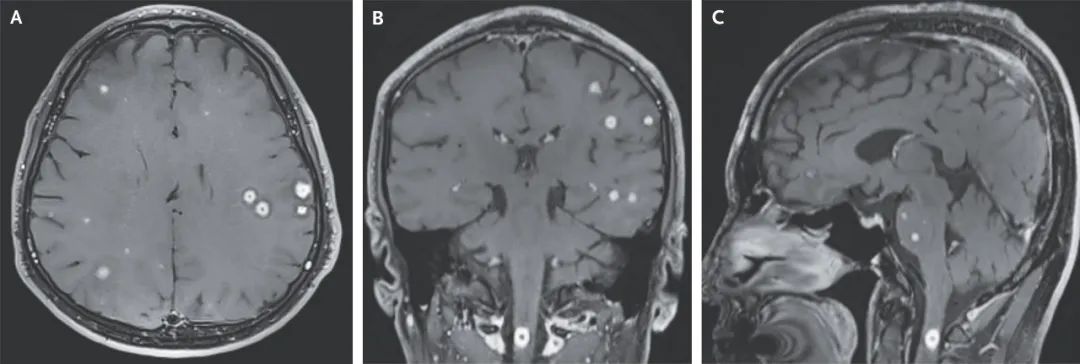

近期發表在《新英格蘭醫學雜誌》上的一項病例中,醫生對一位57歲的患者腦部進行了磁共振成像(MRI),卻意外發現,他的腦子變成了一片“星空”。

在圖中可以看到,這位患者的MRI結果顯示,他的腦子中有許多顏色明亮的“結節”,而這位患者也反饋,他近期出現了不明原因的頭痛、頸部疼痛和右手刺痛症狀,而這種症狀的確清晰地呈現在了掃描結果中。

其實這是一種結核瘤,一般來説在原發性結核感染後,結核塊最終形成的腫塊,有可能出現在任何器官中,比如大腦、腸道、肺、骨骼等。

這是因為結核分枝桿菌,也就是導致致命傳染病——結核病的細菌,它行蹤隱匿,致死率很高,會隨着血液傳播到全身。而對於這位患者來説,研究者提到,結核分枝桿菌會先感染巨噬細胞,巨噬細胞就像一個“特洛伊木馬”,能帶着結核分枝桿菌穿過血腦屏障,進入人的大腦。

所幸,這名患者在服用一些抗生素和消炎藥後就痊癒了。不過,大腦中出現“星空”,往往不是什麼好事。除了像這樣的結核瘤之外,還曾記錄過寄生蟲感染中樞神經系統的疾病。有一種名為豬囊尾蚴病的寄生蟲病,可能會由於食用生豬肉而導致癲癇發作,使得腦部出現這種密密麻麻的病變。